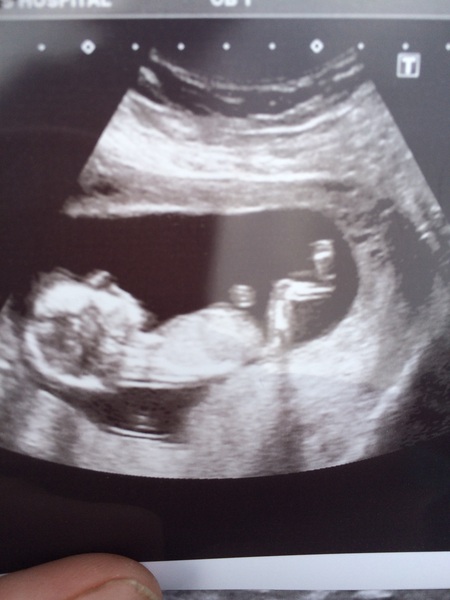

Popping back in as I had my first scan yesterday. Was so worried about it but baby was wriggling around happy as Larry and is set to be another big one...93rd centile for length.

NiceCupOfTeaAndASitDown · 04/08/2016 08:24

Here's my little bean Smile

Nice pic nicecup your baby has very long legs by the looks of things!

Congratulations Nicecup. That's a really lovely clear picture Smile

nicecup lovely pic, baby does look tall!

That's a good photo of your lo, nicecup!